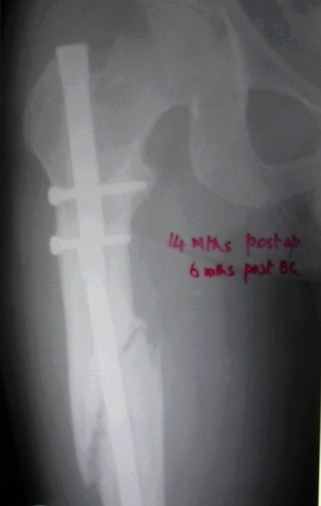

Failure to close 4/4 cortices 6 months post-op definitely meets definition criteria of non-union. Obviously, fixation has failed in this case and needs to be achieved via exchange nail.

Tough to tell from these x-rays, but fx ends appear sclerotic with bridging callus partially present - likely hypertrophic non-union, but you can do a bone scan to confirm viability.

VMI> Kindly note. a) the nail is going towards the medial aspect

VMI> of the lower end thus causing a 5* varus at the # site. b) there

VMI> is a slight overiding causing a centimeter of shortening.

It is agreed by almost all that this is a hypertrophic nonunion.

It has been proved beyond any doubt by experience and literature that hypertrophic nonunion does not need bone grafting but only stabilisation. That is because the reason for NU in this case is instability. This stabilisation can done by 1) rigid plate fixation , 2) ring fixator, by itself or with distraction. (GSK et al), or 3) by thick nail properly locked above and below. I have not done bone grafting for such a nonunion in the last 25 years and have not regretted. So bone grafting, as an additional safeguard measure, is not essential except to protect yourself at the consumer court. (Marco, Bhayendra, Sunil, Abhay, Yasir and Sanjay) The second point is : Is there sufficient amount of angulation and overriding that the the fracture needs to be realigned? If the answer is yes, then only the question of doing it by distraction (Alex) or by opening disengaging the fracture and realigning (Abhay, Yasir and Sanjay)